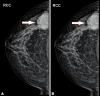

Metaplastic breast carcinoma (MBC) is a general term defining a heterogeneous group that includes biphasic lesions, with both malignant epithelial and mesenchymal tissue components. Although its clinical findings are similar to those present in invasive ductal carcinoma, it rarely presents with the findings of inflammatory breast cancer. It is generally seen in the fifth decade. MBC spreads via lymph and blood circulation. Most common distant metastasis areas include lungs and the bone. Although the treatment generally relies on the same principles applied in invasive ductal carcinoma, a more aggressive treatment should be employed in at-risk groups due to higher rates of local recurrence. In this study, we aimed to discuss clinicopathological features and treatment approach in 5 women with MBC.

- Yang WT, Hennessy B, Broglio K, Mills C, Sneige N, Davis WG, et al. Imaging differences in metaplastic and invasive ductal carcinomas of the breast. AJR Am J Roentgenol. 2007;189:1288–93. - PubMed